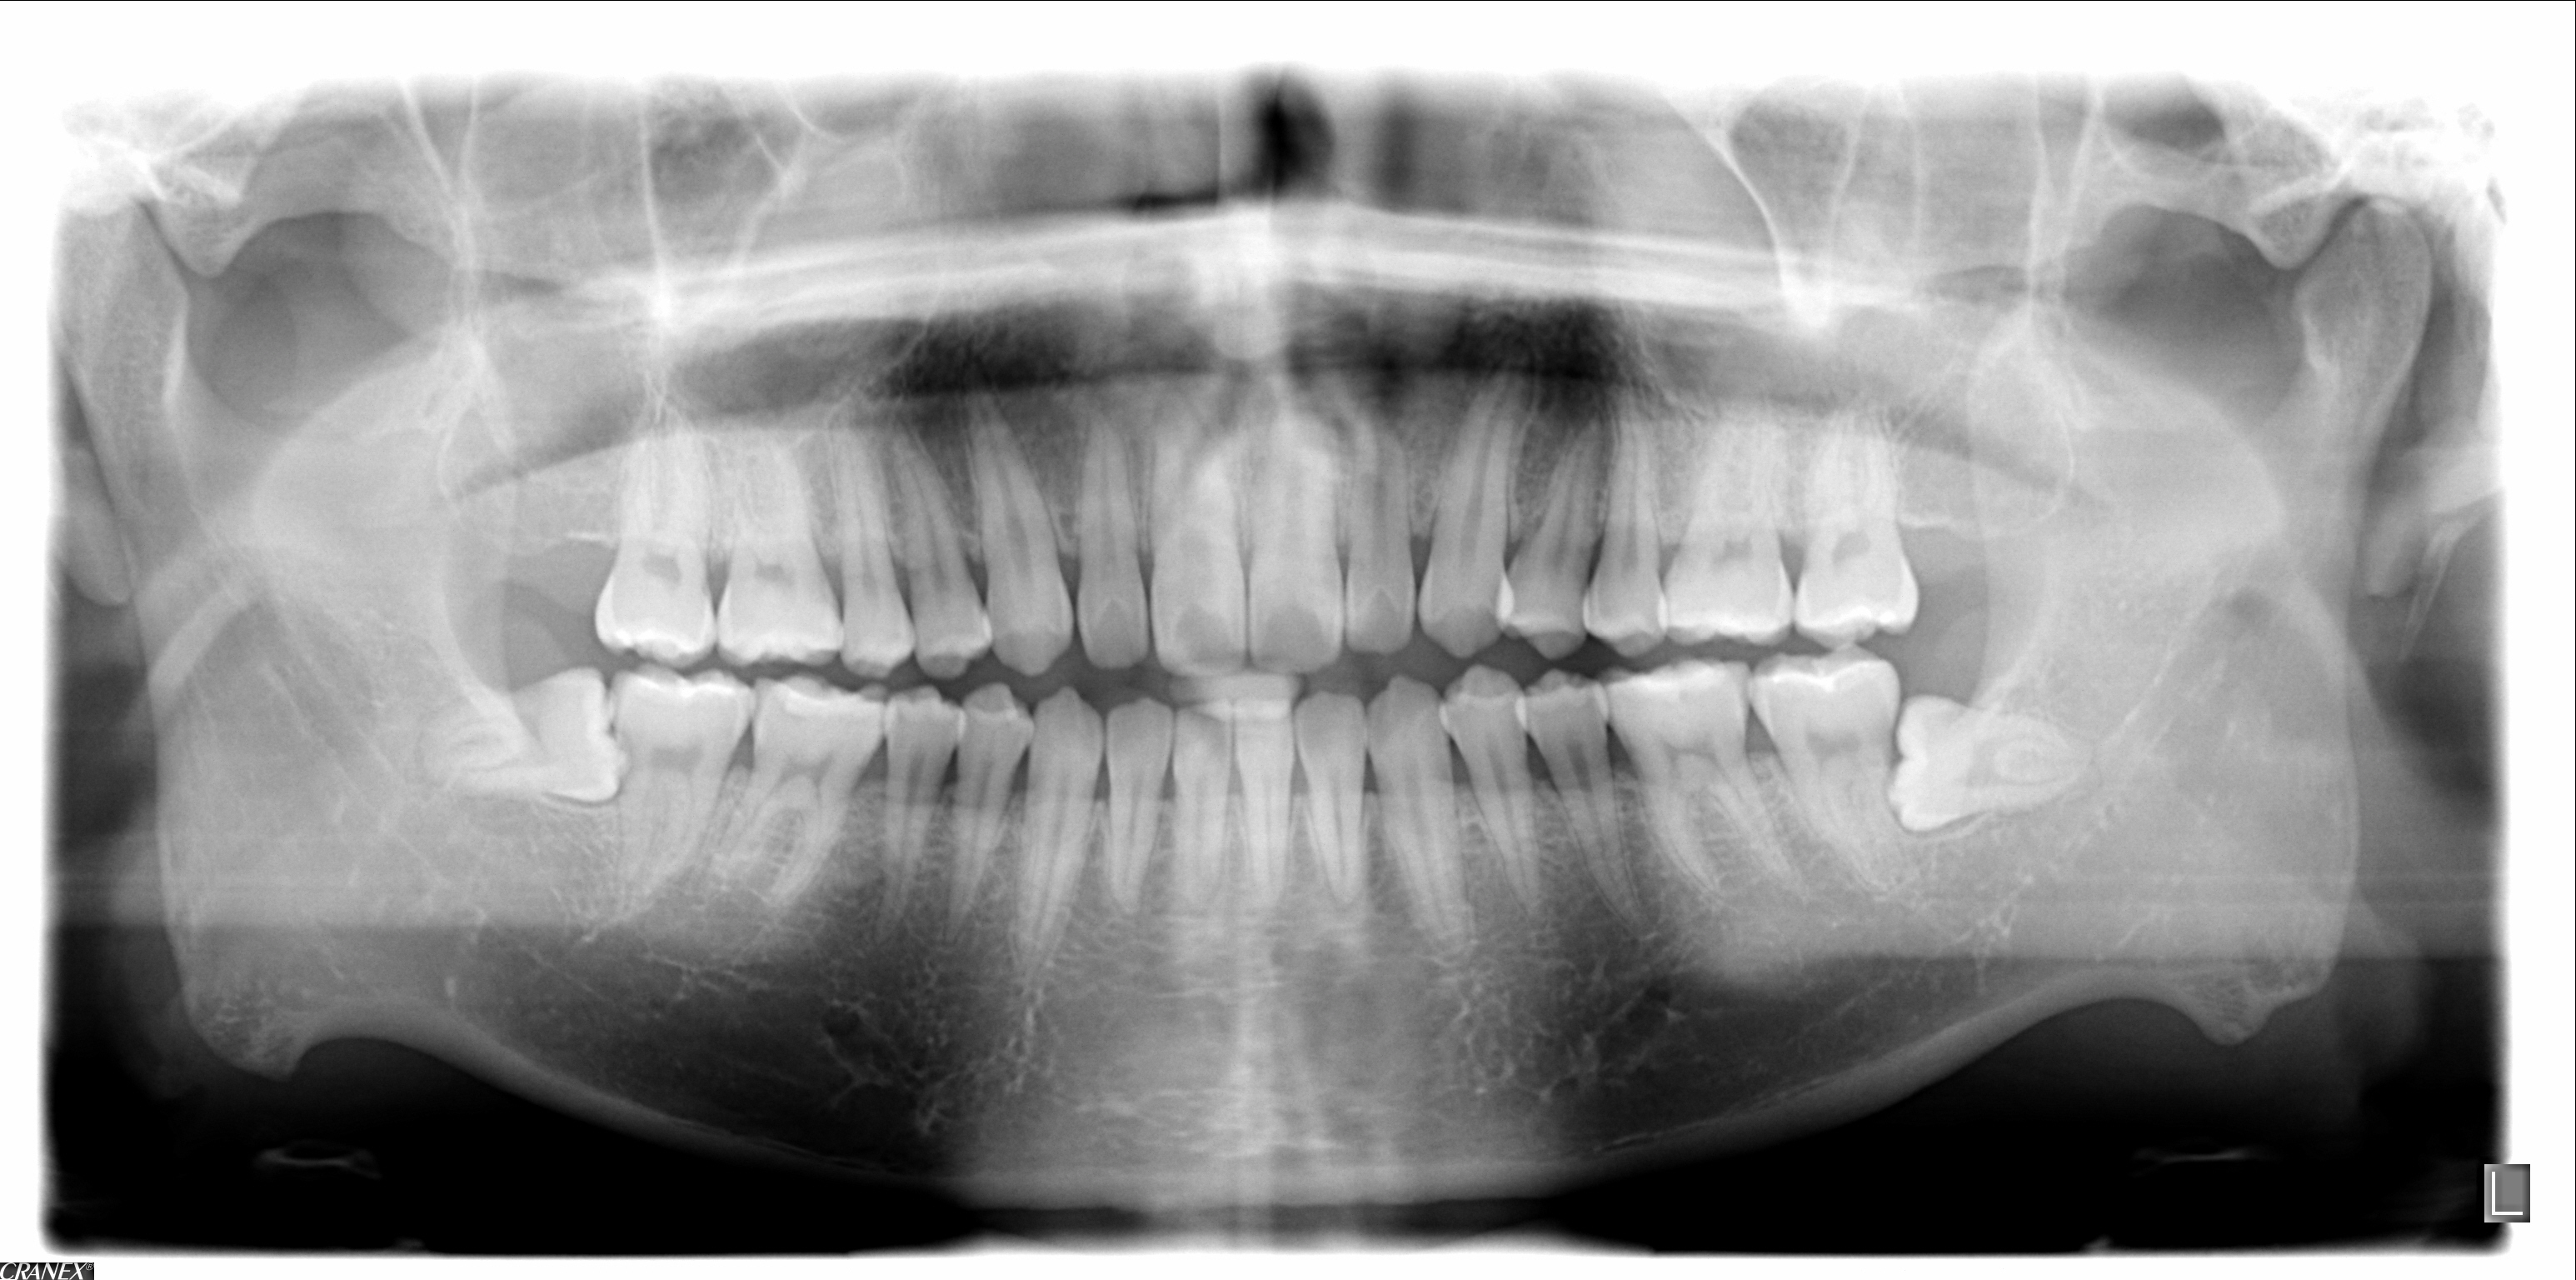

< 매 복 치 >

정상적인 시기에 잇몸 밖으로 나와야 할 치아가 잇몸 속에 그대로 남아 있는 것이며

잇몸 속에 있기 때문에 특별히 문제가 되지는 않으나 주변으로 염증이 생긴다 거나

통증이 느껴질 시에는 발치를 하여야 합니다.